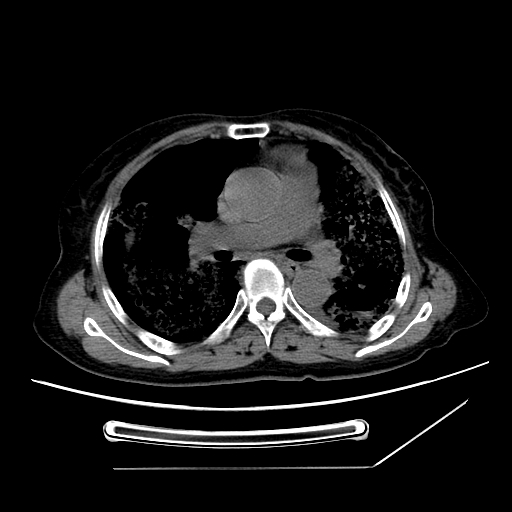

标题: CT25393:病人45岁,咳嗽,吐黄痰带血丝,发热,胸闷月余 [打印本页]

标题: CT25393:病人45岁,咳嗽,吐黄痰带血丝,发热,胸闷月余

1、左肺中央型肺癌并双肺弥漫性转移   2、双肺部感染    3、肺大泡     4、左侧胸腔积液

双侧肺弥漫性病变,可见“空泡征”及“蜂窝征”,考虑肺泡癌可能性大,左侧胸腔积液,考虑胸膜受累可能!

1)不排除肺泡癌可能。2)左侧胸腔积液。